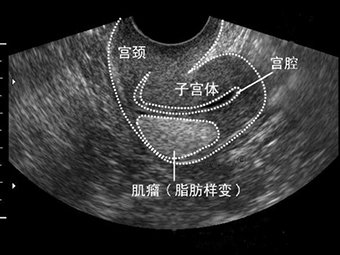

2 子宫肌瘤 不是一切了之

子宫肌瘤有女性生殖健康的“潜在杀手”之称。每3个女性中就有一个子宫肌瘤患者。子宫肌瘤是女性子宫体上长了肌瘤,也被称为子宫平滑肌瘤,是女性生殖器官最常见的良性肿瘤。预防子宫肌瘤,要求妇女在经期及产后要特别关注,严禁房事,保持外阴和阴道清洁,心情舒畅,减轻压力,关注保暖,禁止饮用生水,饮食宜清淡,易消化,忌食辛辣生冷刺激性食物,保持正气充足气血顺畅。

很多女性得了子宫肌瘤,见到医生第一句话就是,给我切了吧。其实不然,治疗子宫肌瘤的方法要视具体情况而定,并非一“切”解千愁。症状轻的患者,若子宫大小不超过孕12周的大小,则不必手术,只要每3个月去医院复查一次,随时关注肌瘤的变化即可。特别是针对近绝经期的患者,因其绝经后肌瘤有自然萎缩的可能,所以一般都主张保守治疗。